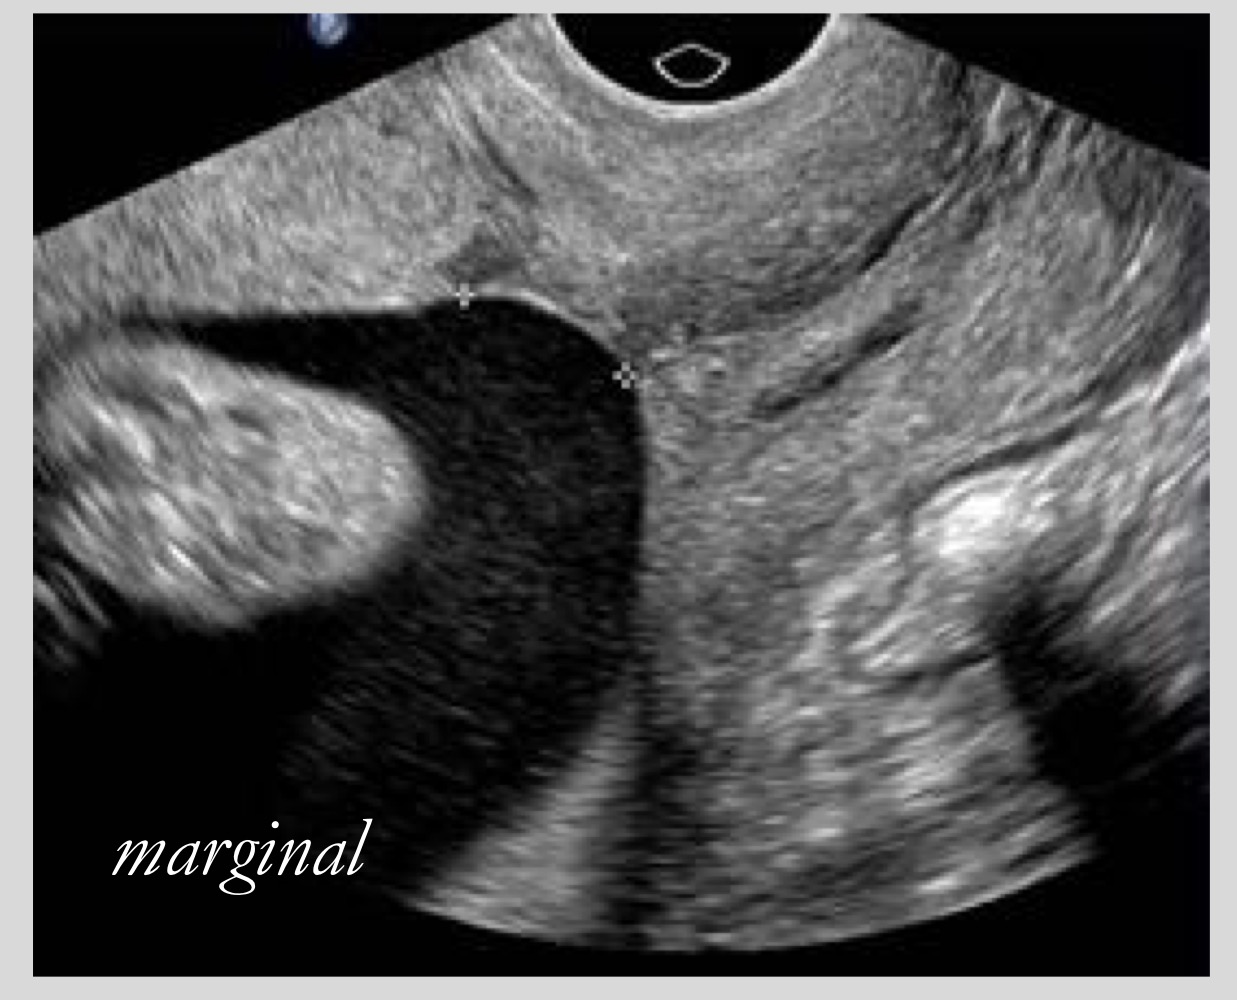

Definition of marginal or low-lying placenta

Placenta is within 2 cm of the internal os but not covering it

What distance defines a low-lying placenta

Within 2 cm of the internal os

How is placenta previa measured

From internal os to the placental edge

What are the two main types of placenta previa

Low-lying (marginal) and complete